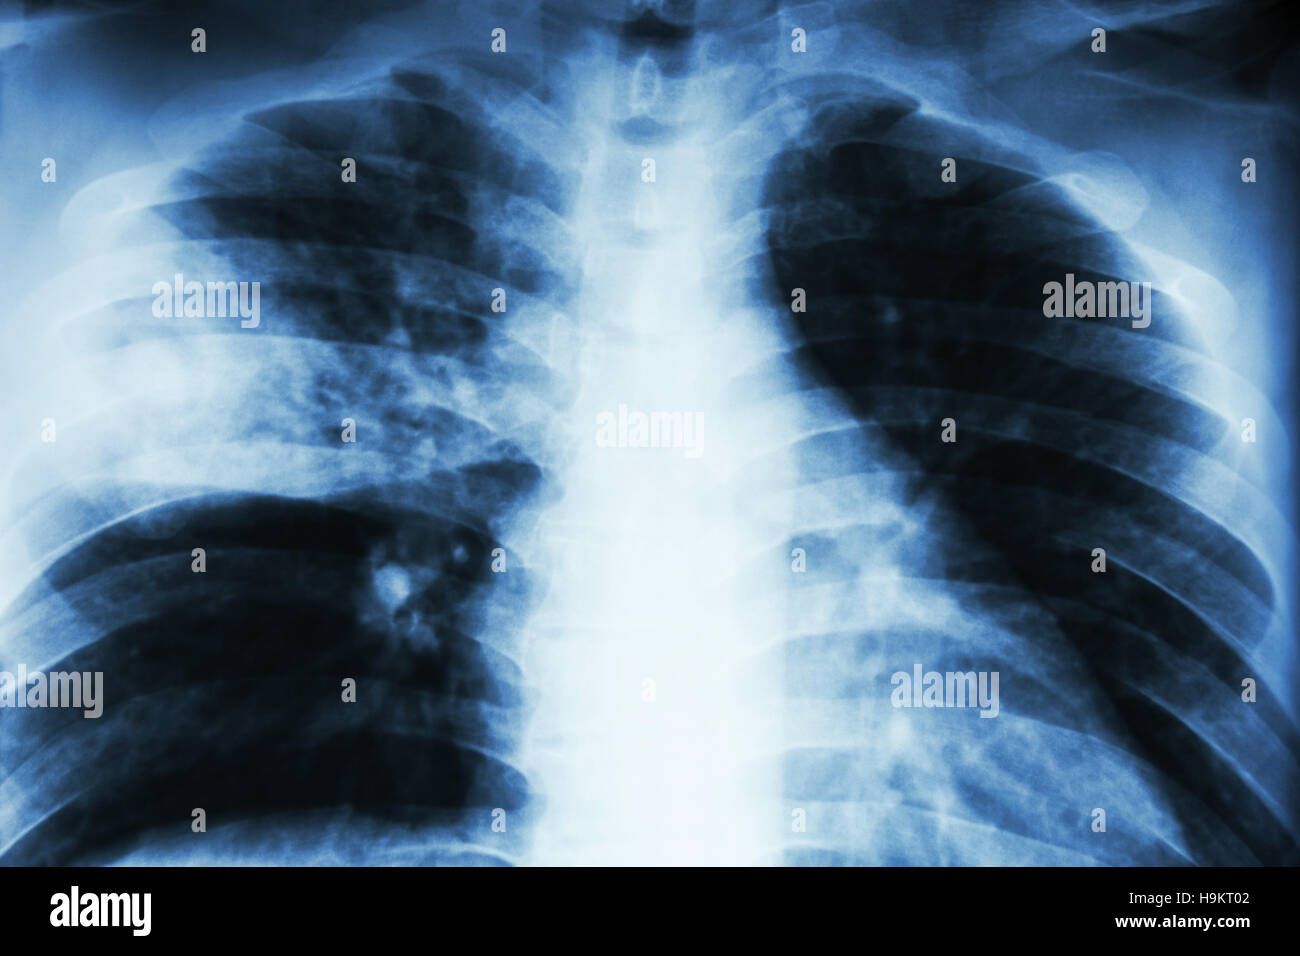

Chest X Ray Lobar Pneumonia . One of the primary roles of chest radiography in emergency department patients is to diagnose pneumonia. This image shows consolidation of the right upper lobe which is confined inferiorly by the horizontal fissure; This must be followed by invasive sampling techniques like mini broncho. If the consolidation is due to infection, then the term ‘lobar.